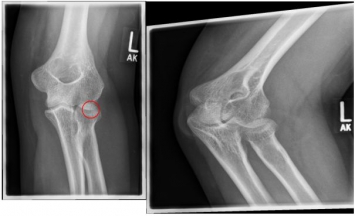

Photo: An undislocated fracture that can be treated conservatively.